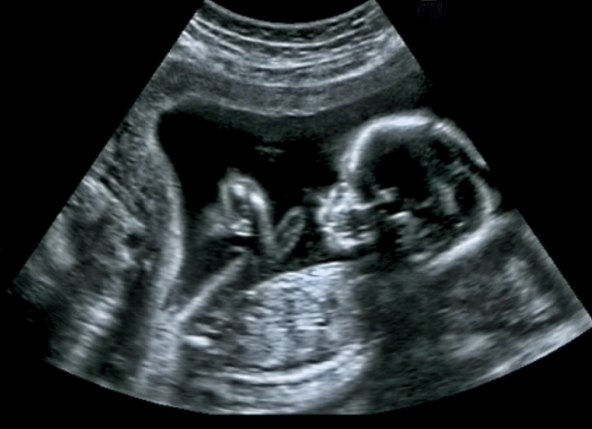

Tijekom ultrazvuka u drugom tromjesečju liječnik će provjeriti strukturu bebina srca i provjeriti postoji li kakva urođena greška.